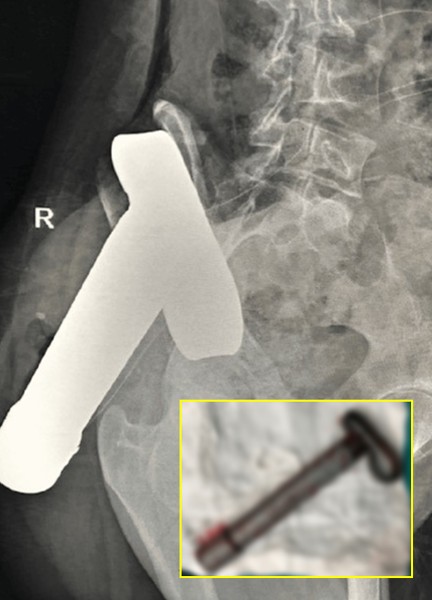

인도 히말라얀 의과대학 정형외과 의료진에 따르면, 16세 여성이 오토릭샤(3륜 택시)를 타고 이동하다가 과속 차량과 정면충돌했다. 사고 당시 철제 막대가 튀어나오면서 여성의 오른쪽 둔부를 관통했고, 몸 안에 깊이 박히면서 혼자 움직일 수 없는 상태가 됐다. 현장에 있던 시민들은 철제 막대 일부를 절단해 구조한 뒤 여성을 병원으로 긴급 이송했다.

다행히 여성은 의식이 명료한 상태였다. 다만 철제 막대가 몸 안에 남아 있었고, 영상 검사 결과 둔부 근육을 지나 골반까지 관통한 것으로 확인됐다. 의료진은 정형외과와 일반외과로 구성해 제거 수술을 시행했다.

그 결과, 주요 장기와 관절은 손상되지 않은 채 철제 막대를 제거했다. 여성은 큰 합병증 없이 3주간의 입원 치료를 받은 후 퇴원했다. 의료진은 “이번 사례는 심각한 관통 외상에도 신속한 처치와 수술이 생존에 결정적인 역할을 했다는 점을 시사한다”고 말했다.